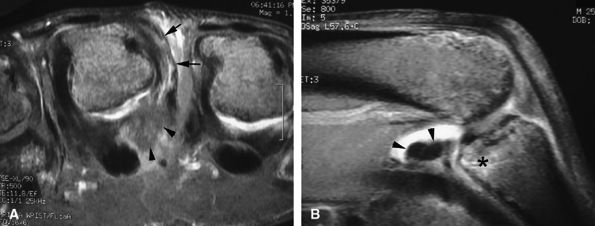

FIGURE 11.47 ● Jersey finger. (A) Sagittal T2-weighted image. (B) Coronal post-contrast T1-weighted images. (C) Axial T1-weighted image. Distal avulsion of the FDP tendon is shown with the proximal end (white arrows) at the metacarpophalangeal joint (type I). The tendon is wavy in the palm (arrowheads). The empty digital canal (in C) may mimic a remnant tendon, but the FDS tendon (asterisk) is alone in the canal.